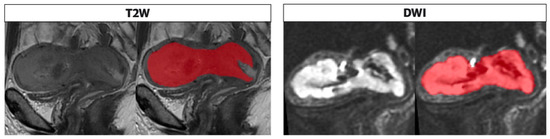

The whole tumor segmentations were performed by a radiologist (V.C.) with 4 years of expertise in gynecological imaging who manually outlined the region of interest (ROI) on the T2WI and DWI along tumor boundary on each slice; the segmentation was subsequently reviewed by senior radiologist with 25 years experience in pelvic female tumors (L.M.) (Figure 3). The radiologists were blind to the clinical and pathologic outcomes. The segmented tumor area appeared as intermediate/low intensity compared to the normal myometrium for T2WI, while it appeared as high intensity for DWI.

Figure 3. Segmentation performed on T2 and DWI sequences in the sagittal plane along the tumor boundary. The endometrial cavity is replaced by solid heteroplastic tissue characterized by intermediate signal intensity in the T2 sequences and high signal compared with the neighboring myometrium in the DWI images; the tumor is bounded by the red area as shown in the figure alongside both sequences as performed in the segmentation process, on the T2 and DWI.